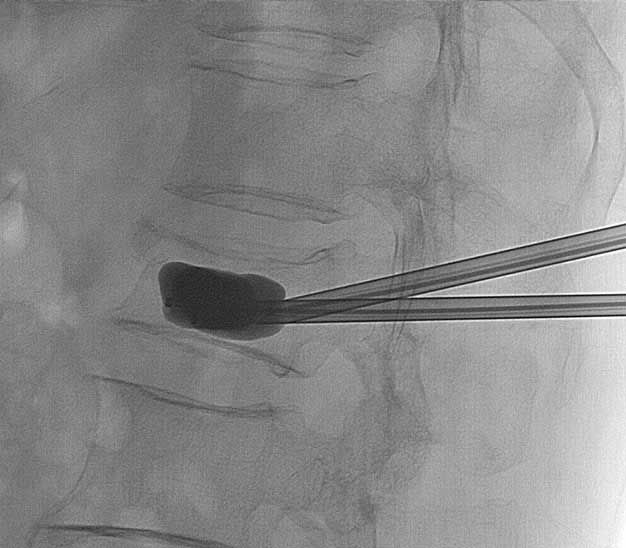

O tratamento cirúrgico para as fraturas da coluna é reservado para uma minoria dos casos. Ele está indicado nas lesões instáveis ou que apresentam lesão neurológica associada. Existem diversas opções de tratamento cirúrgico, desde procedimentos minimamente invasivos (fixações percutâneas, cifoplastia, etc…) até procedimentos abertos tradicionais (artrodese anterior, artrodese posterior, etc…). O tipo de tratamento cirúrgico necessário para cada caso deve ser indicado por um  médico especializado.

fratura na coluna cifoplastia